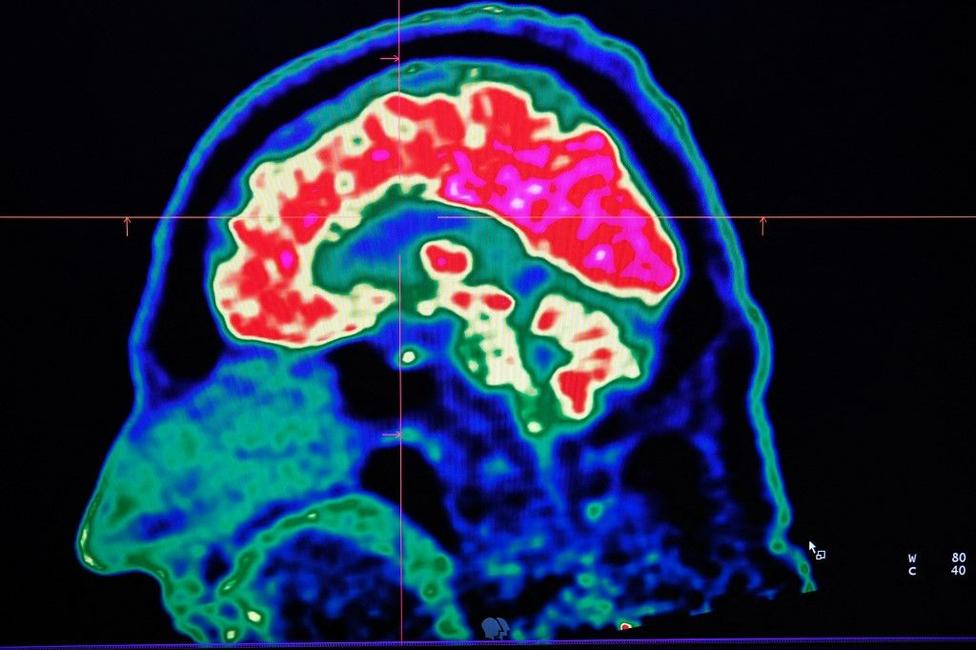

Oublier ce qu'on était venu faire dans une pièce, un phénomène qui continue d'interroger les neuroscientifiques.

En étant focalisés sur nos pensées, il peut nous arriver d'oublier ce que nous étions venus faire dans une pièce. Le concept du "doorway effect" explique que le passage d'une porte entre deux pièces y est sûrement pour quelque chose. Une nouvelle étude apporte d'autres explications.